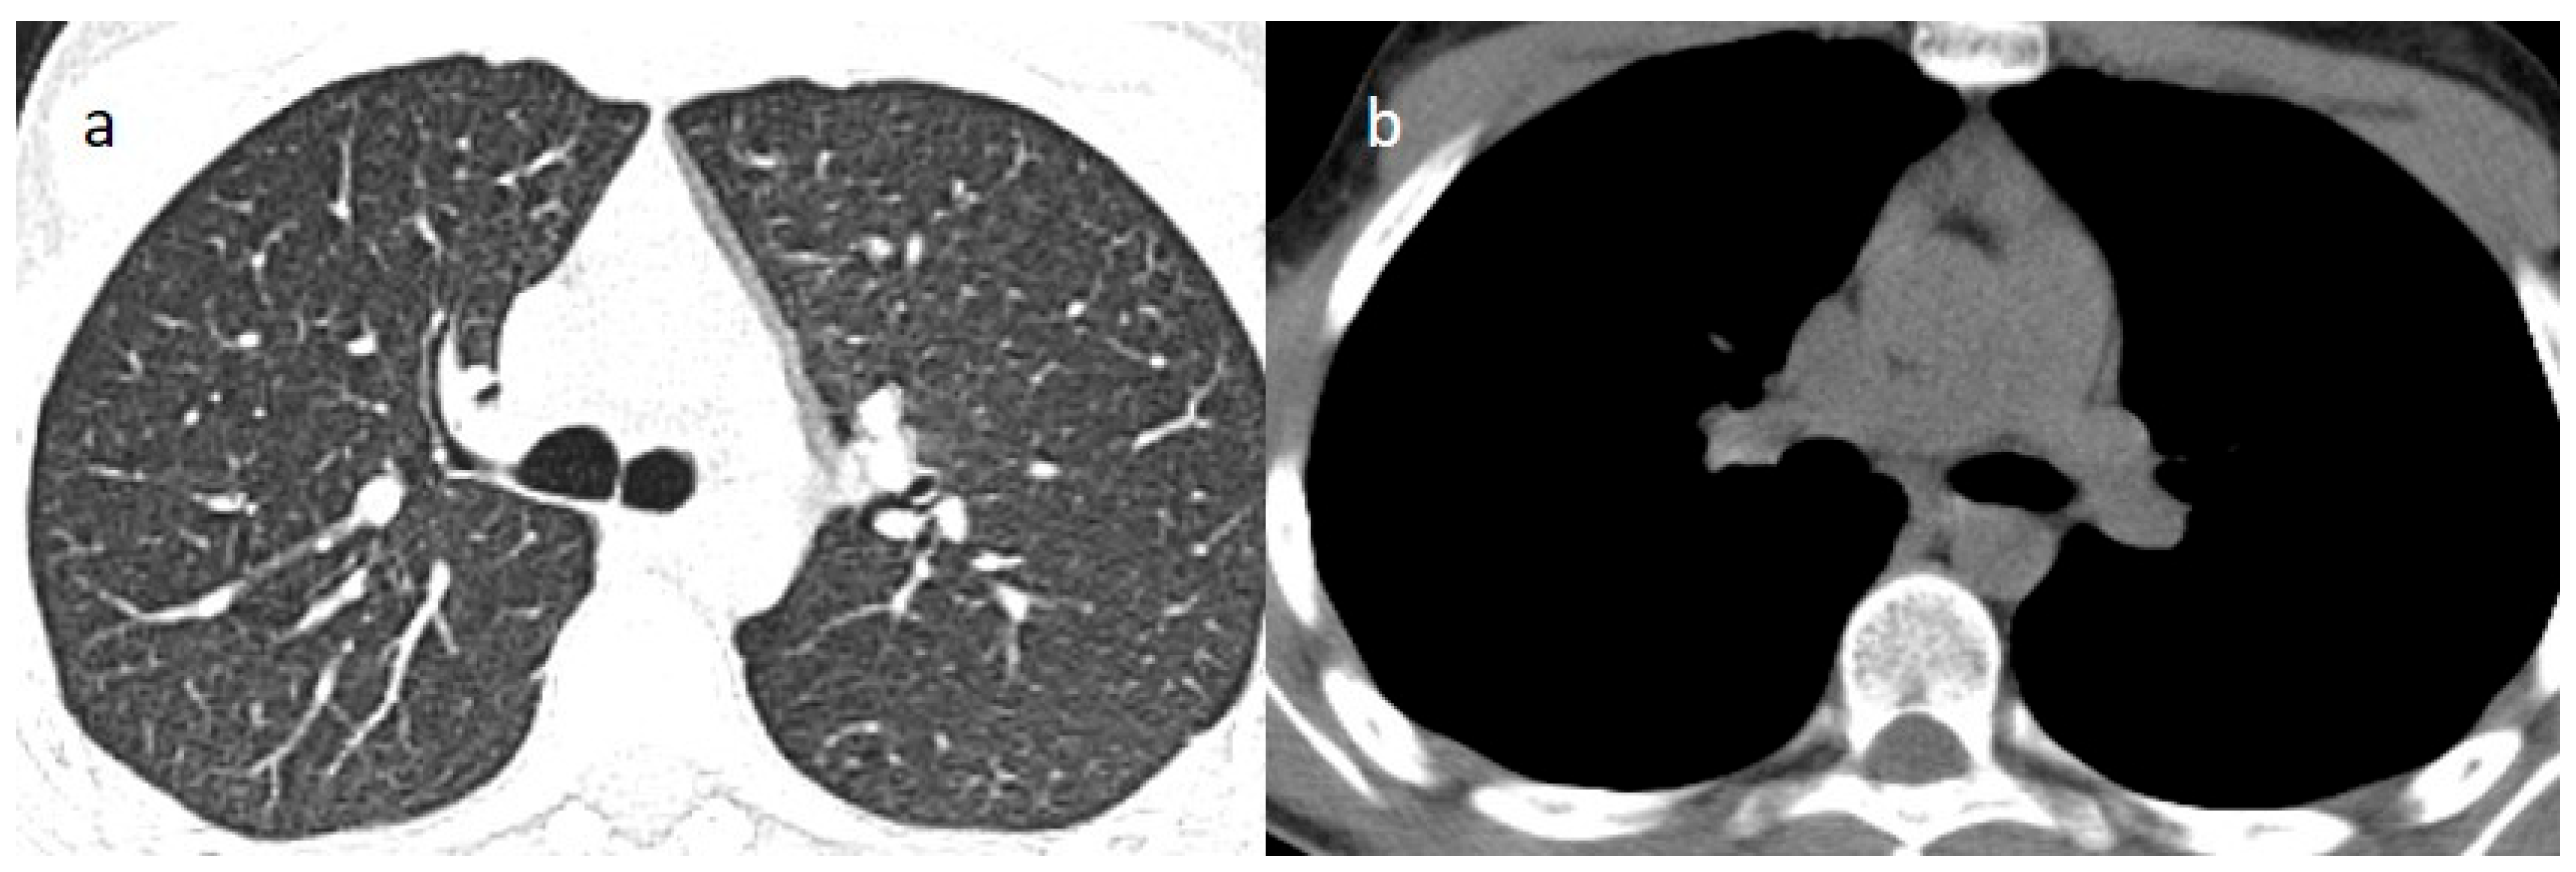

2. Case Presentations